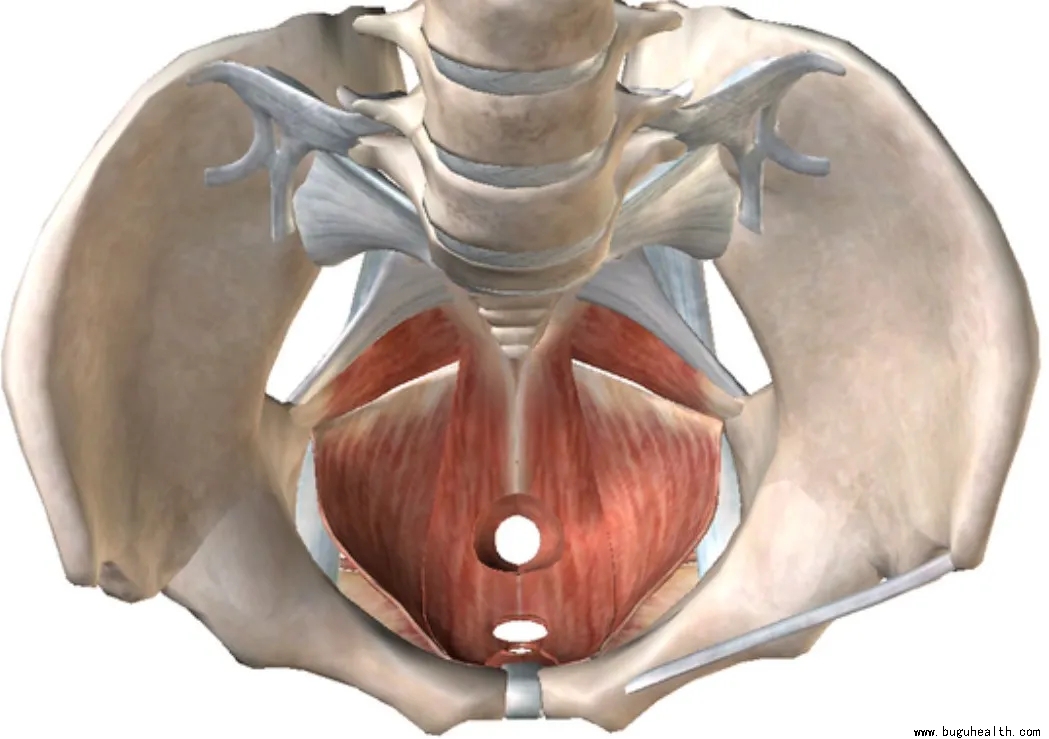

�������������Ҫ�ṹ֮һ���������ϰ������������ֿ������°����Ķ������м�ʮ��������֯�������Ե�����������������Ҫ���á�